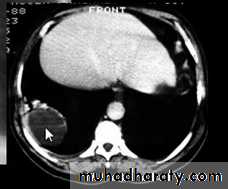

Pericardial Cyst.

Enhanced CT scan through heart shows a smooth, sharply marginated, low-attenuation mass (arrow) in the right cardiophrenic angle, consistent with a pericardial cyst.